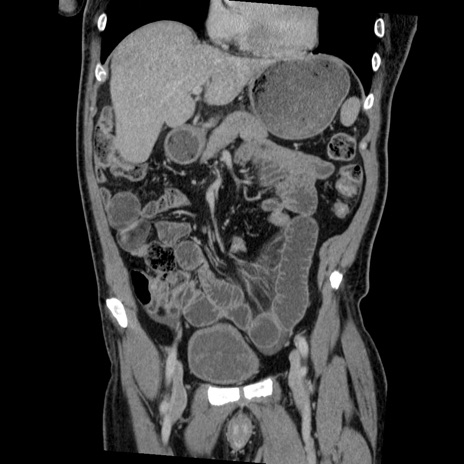

症例22(冠状断像)

【症例】50歳代男性

【主訴】腹痛

【現病歴】AVMからの被殻出血のため回復期リハ病棟入院中。 本日午後3時頃急に下腹部痛が出現した。

【既往歴】AVM、被殻出血、虫垂炎、高血圧

【身体所見】意識晴明、左半身不全麻痺、会話の理解は良好、36.5°C、腹部:膨隆、全体に板状硬、下腹部正中に圧痛点あり、反跳痛-、筋性防御不明、右下腹部にope scar

【データ】WBC 9400、CRP 0.06